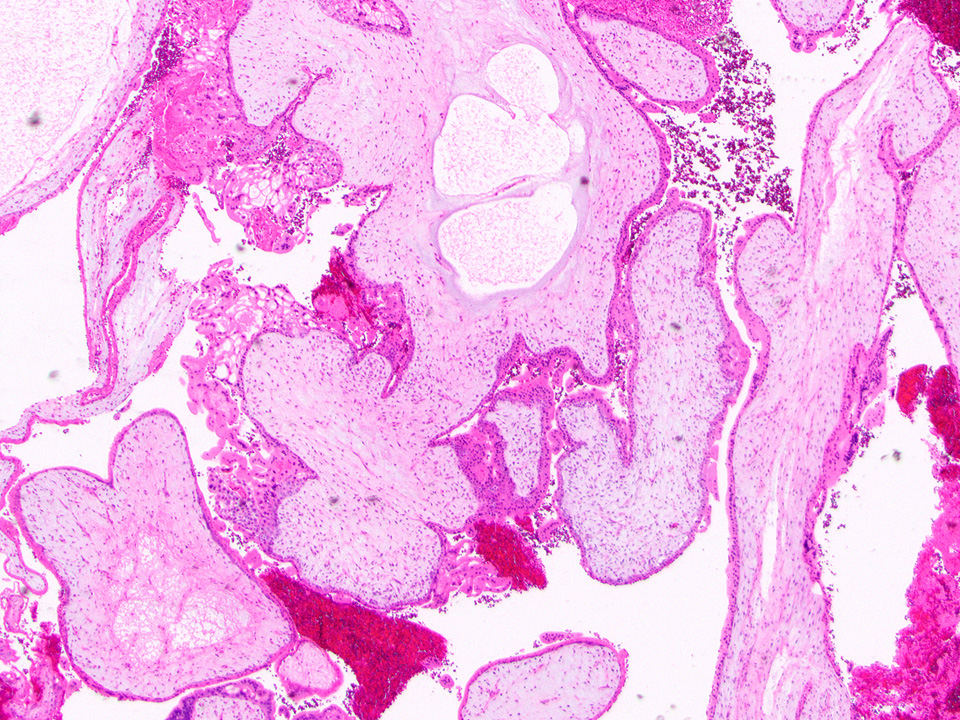

Gross description

- Specimen often consists of fragments of placental tissue (chorionic villi, membranes / gestational sac that may be intact or disrupted and decidua)

- Despite identification of embryo or fetus on ultrasound, an embryo is often not identified / recognized in surgical specimens (J Clin Pathol 1981;34:819)

Microscopic (histologic) images

Contributed by Chrystalle Katte Carreon, M.D. and Drucilla J. Roberts, M.D.